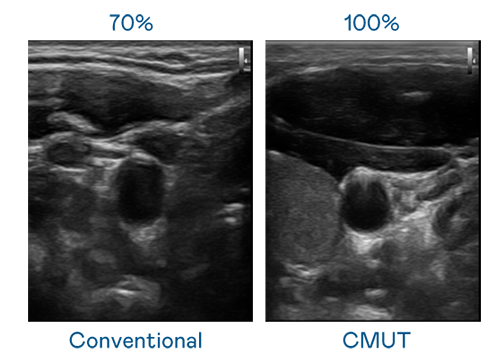

CMUT 技术是一种用电容式微机电元件来产生超音波讯号的技术。与传统 PZT 压电式技术相比,CMUT 频宽增加 30%,更宽频的超音波讯号让影像解析度大幅提升,是实现高影像品质医疗超音波扫描、促进精准医疗发展的关键技术。

大频宽带来超清晰影像

超音波影像的解析度高低,首先取决于探头能发出的讯号频宽。谈球吧 CMUT 可提供高清晰的超音波讯号,提供高频宽、高灵敏度、影像纹理细节更高的超音波影像,协助医护人员缩短影像判读时间及利用精准的医疗影像进行诊断。